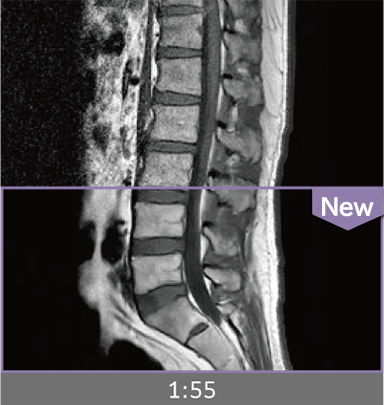

Images can be obtained at high speed by combining two technologies: IP-RAPID, which reduces imaging time while maintaining image quality, and Advanced Reconstruction to improve image quality.

Under-sampling reduces imaging time, and iterative reconstruction with IP-RAPID reduces noise and artifacts.

In addition, Advanced Reconstruction further eliminates noise and produces images that are easier to use in making a diagnosis.